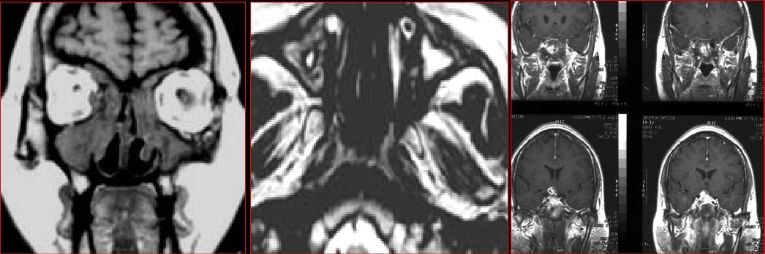

慢性多发鼻窦炎—MRI

MRI表现:

★ 侵袭为黏膜炎性水肿和蜂窝织炎,T1WI为低信号,T2WI为高信号

★ 慢性为明显低信号,钙化,霉菌内含有铁和锰等顺磁性物质,含蛋白质高的黏液等。

★ 反应性肉芽肿或鼻窦炎T1WI为低信号、T2WI为高信号

★ 增强扫描病变周边黏膜明显强化

★ 显示侵犯眼眶、颅底、颅内实质或硬脑膜窦